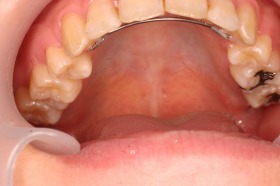

ご覧の症例は出っ歯を矯正治療でキレイにしたケースです。

このような場合では歯を抜いて矯正するか

、抜かずに矯正するか分かれるケースです。

ご覧の矯正歯科治療の場合は、抜いて矯正歯科

治療していますが東京世田谷矯正歯科センターでは

非抜歯矯正歯科治療をベースにしています。

どうしても抜かないとキレイにならない場合のみ

抜歯して矯正歯科治療しています。